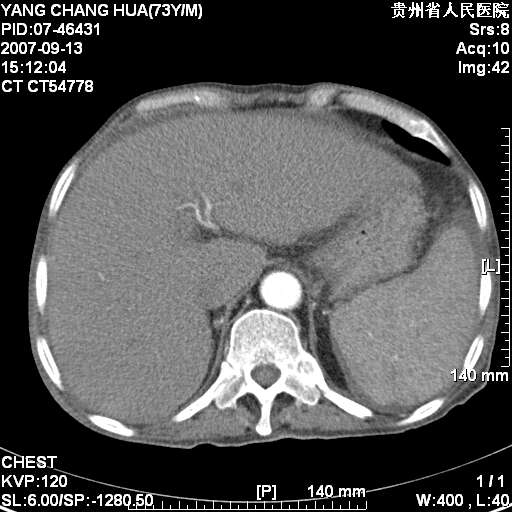

图像没有传全。肺部为感染性病灶;肺囊肿;双侧胸腔积液;肝脾肿大;腹水。

双肺部为感染性病灶.双侧胸腔积液;肝脾肿大;腹水.

双肺部为感染性病灶.双侧胸腔积液;肝脾肿大;脾脏密度不均,不除外脾侵润?腹水.

双肺部为感染性病灶.双侧胸腔积液;肝脾肿大;腹水

图片不全.就这几张图片.无法诊断淋巴瘤的,我考虑:双肺部为炎性病灶.双侧胸腔积液;肝脾肿大;腹水

双肺点片状影,以双上肺改变明显.双侧胸腔积液.为感染性病灶,但不除外结核.

肝脾都大..

肝脾肿大。

少量腹水。

双肺散在斑片状及多发小结节状阴影,边缘模糊,双上肺野明显,双侧胸膜腔少量积液,纵隔及肺门区未见明显肿大淋巴结,肝脾肿大,脾内见多发低密度区,结合临床考虑恶性淋巴瘤(肺内表现为肺炎肺泡型),单看影像表现,肺结核不能排除。建议结合实验室检查或表浅淋巴结活检。

肺部为;恶性淋巴瘤;双侧胸腔积液;肝脾肿大;腹水。